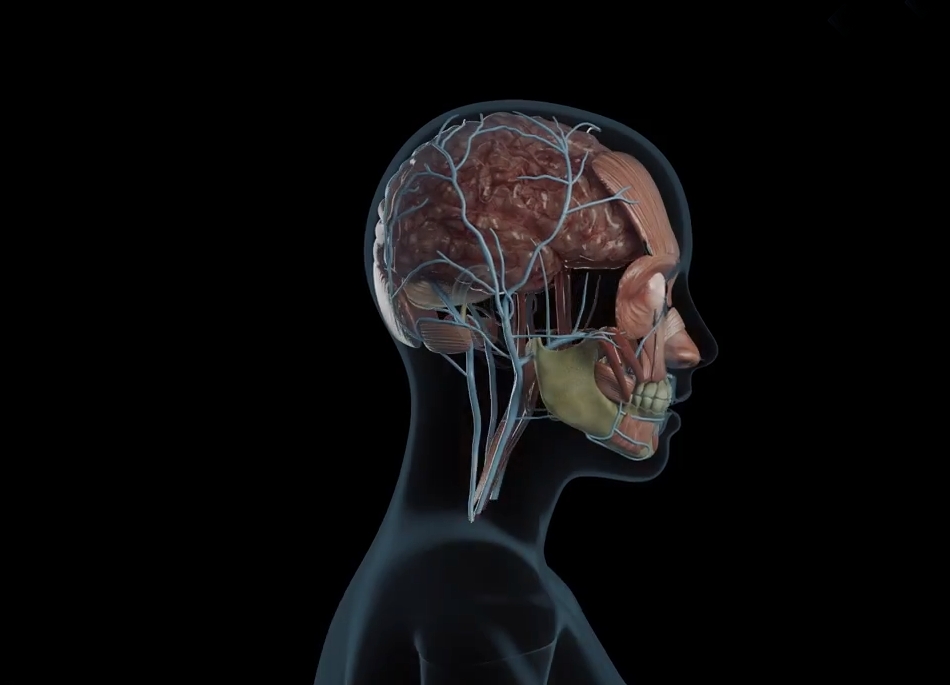

3d Medikal Tanıtım Filmleri - Medikal sektör için 3D ilaç tanıtım filmleri.